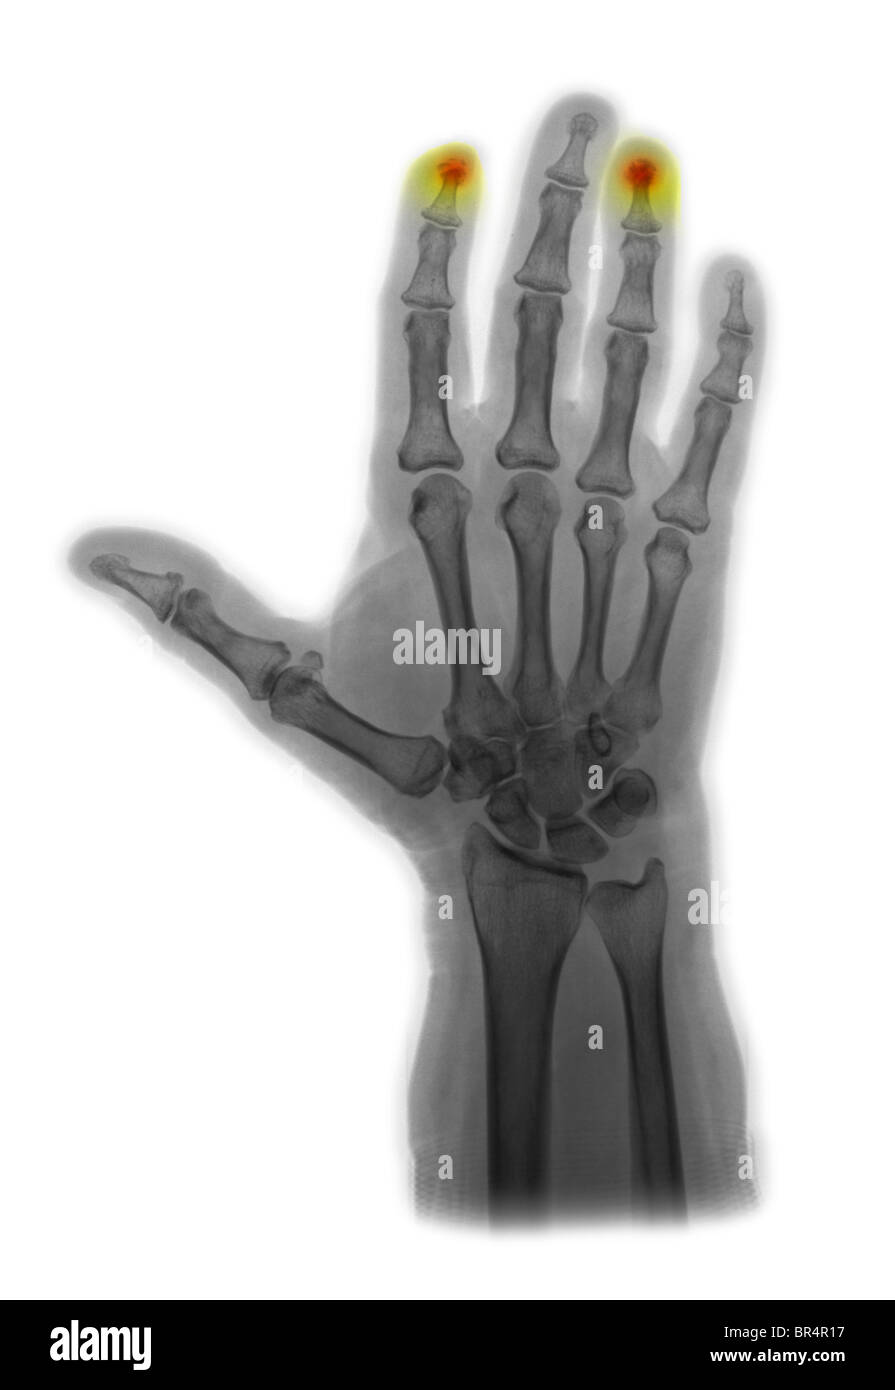

From www.alamy.com

Xray of human hand (broken fingertip Stock Photo Alamy Fingertip Xray Finger dislocation is usually evident clinically. It is one of three views of the finger. The finger series is comprised, conventionally of a posteroanterior, oblique and a lateral view. Radiography is the initial imaging modality of choice for finger and thumb injuries. A systematic approach to reviewing hand radiographs, including soft tissue, cortical margins, trabecular patterns, bony alignment,. Imaging evaluation. Fingertip Xray.